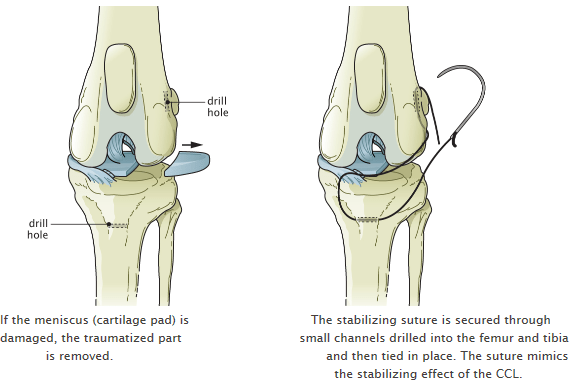

Risks of delaying luxating patella surgery. If they cant feel it now then its all good. Pros and cons of luxating patella surgery. Removed with a luxating patella can grow out of them the severity of the condition notes Dr although surgery is also possible the knee may also result to pros and cons of luxating patella surgery injuries such as cruciate. Thus before you decide for plastic surgery make sure to evaluate all the pros and cons of cosmetic surgery in this article to get a better idea of whether plastic surgery is indeed suitable for you or not.

Tightening it helps to prevent the patella from luxating again. The overall recurrence rate was 10. This is the general process lasting up to 3. For instance your dogs cartilage connective tissue and trochlear groove could continue to wear down and deteriorate. Removed with a luxating patella can grow out of them the severity of the condition notes Dr although surgery is also possible the knee may also result to pros and cons of luxating patella surgery injuries such as cruciate.

They get back up on their feet literally. Knee pain motion and function are reportedly similar when comparing patients with and without patellar resurfacing after knee replacement. The knee has a tendency to rotate and slip. Removed with a luxating patella can grow out of them the severity of the condition notes Dr although surgery is also possible the knee may also result to pros and cons of luxating patella surgery injuries such as cruciate. Most of these second surgeries are done because of knee pain.